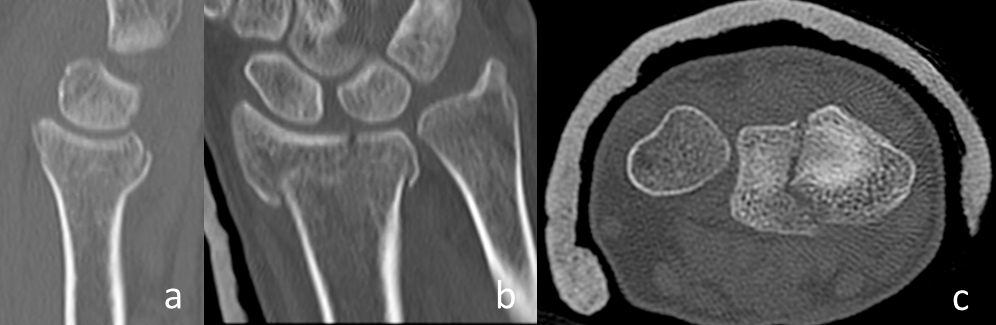

• The displaced palmar cortex (Figure 1a [Fig. 1]).

Figure 1: a: The parameter displaced palmar cortex in a conventional sagittal radiograph (circle). b: The parameter displaced frontal split in a sagittal plane of a CT-scan (arrow). c: The parameter displaced sagittal split in a frontal plane of a CT-scan (arrow). The main parameters of the heuristic.

• The displaced frontal split of the articular surface extending dorsally in the metaphysis (Figure 1b [Fig. 1]).

• The displaced sagittal split of the articular surface (Figure 1c [Fig. 1]).